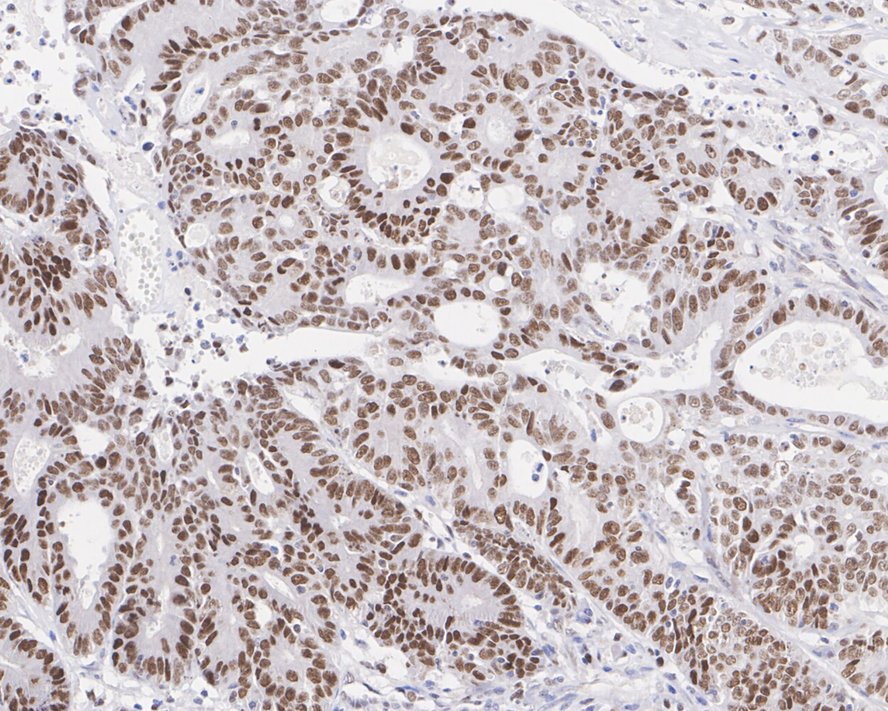

Immunohistochemical analysis of paraffin-embedded human colon cancer tissue with Rabbit anti-KMT6 / EZH2 antibody (ET1701-56) at 1/500 dilution.

The section was pre-treated using heat mediated antigen retrieval with Tris-EDTA buffer (pH 9.0) for 20 minutes. The tissues were blocked in 1% BSA for 20 minutes at room temperature, washed with ddH2O and PBS, and then probed with the primary antibody (ET1701-56) at 1/500 dilution for 1 hour at room temperature. The detection was performed using an HRP conjugated compact polymer system. DAB was used as the chromogen. Tissues were counterstained with hematoxylin and mounted with DPX.